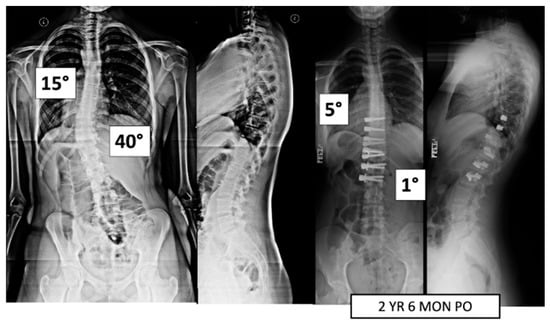

Figure 2.

This is a 15-year-old female treated with lumbar VBT. At 2 years and 6 months post operation, she has resumed all activities with no complications.